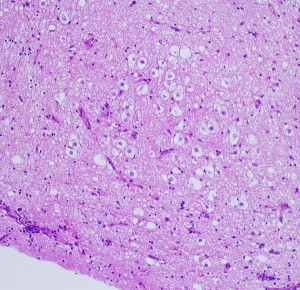

大小の神経細胞とグリア細胞が混在して存在します

小型のグリア細胞にも多少の異型があり腫瘍性グリアと考えられます

グレード1のgangliogliomaです

大脳皮質に大型の核を有する円形の神経細胞が散在しています。神経細胞間にグリア細胞がありますが腫瘍性増殖を示しません。MIB-1は1%以下でした。血管周囲にリンパ球浸潤があります。